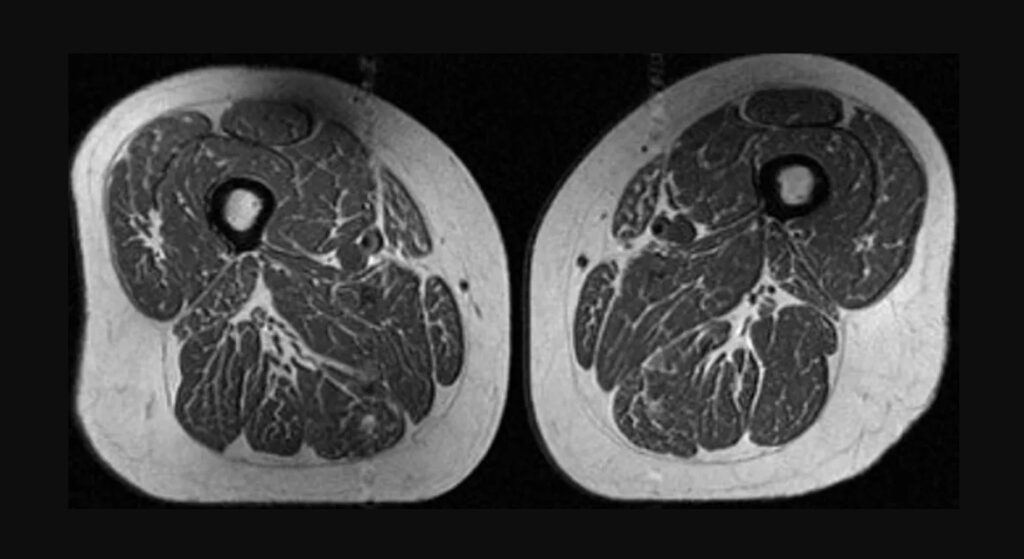

Analiza, bazată pe scanări RMN realizate pe peste 600 de persoane, arată o legătură clară între consumul de alimente ultraprocesate și creșterea grăsimii intramusculare. În unele cazuri, imaginile au relevat mușchi cu un aspect comparat de specialiști cu cel al unei „fripturi marmorate”, din cauza straturilor fine de grăsime infiltrate între fibrele musculare. Cercetătorii au observat că acest fenomen apare chiar și la persoane care nu prezentau semne de osteoartrită, sugerând că degradarea calității musculare începe înainte de apariția simptomelor, scrie CNN.

Grăsimea infiltrată în mușchi afectează capacitatea acestora de a se regenera și reduce forța musculară. În timp, acest proces poate contribui la apariția unor afecțiuni precum osteoartrita genunchiului. Mușchii coapselor sunt esențiali pentru stabilitatea articulațiilor, iar slăbirea lor crește presiunea asupra genunchilor, mai ales în cazul persoanelor supraponderale. Specialiștii avertizează că acest tip de degradare nu este limitat la o zonă a corpului, ci poate afecta și alte grupe musculare, indicând un proces sistemic.